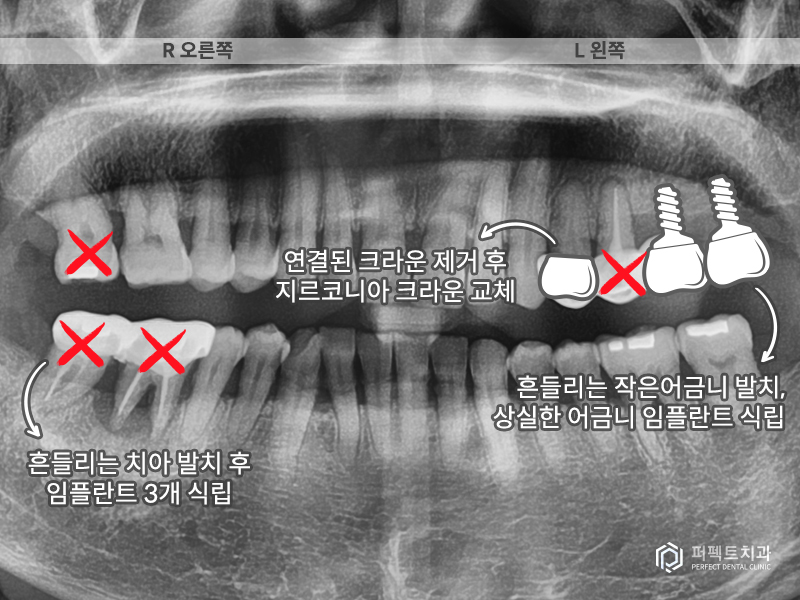

치료 계획은 오른쪽 아래 어금니 임플란트 2개, 흔들리는 위 어금니를 발치하고 1개, 왼쪽은 원래 없던 치아 2개와 옆에 흔들리는 치아까지 총 3개 의 임플란트를 식립하기로 하였습니다.

옆에 있는 치아는 붙어있는 크라운이기 때문에 제거 후 지르코니아 크라운으로 다시 수복하는 계획을 세웠습니다(총 임플란트 6개, 크라운 1개).